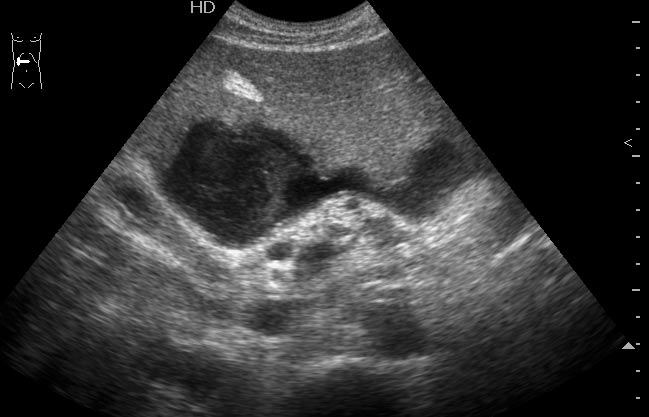

Мужчина средних лет, поступил в хирургическое отделение с диагнозом хронический панкреатит, обострение.

При УЗИ обследовании выявлена такая штука (см ниже). Несколько последних дней температура 39 С

УЗИ: Абсцесс печени

Печень?, абсцесccc>>>>>дренаж

Да.Брехт писал(а):Печень?, абсцесccc>>>>>дренаж

Откуда взялся,не из соседнего ли ж.пузыря,который почти спавшийся и с очень толстыми и расслоенными стенками

Нет, пузырь здесь непричем - он практически не измнён.besliu писал(а):Откуда взялся,не из соседнего ли ж.пузыря,который почти спавшийся и с очень толстыми и расслоенными стенками

Хронический панкреатит.